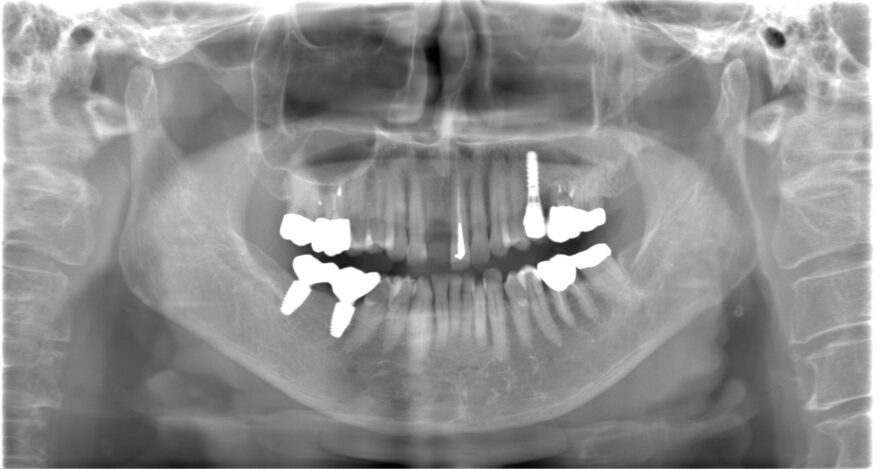

初診時レントゲン写真

このように、前歯の欠損部にブリッジもしくは入れ歯を他院さんで提案されてしまい、当院にご相談に来られる患者様が多数いらっしゃいます。

オペ前のシミュレーション

ほとんどの医院さんで

・前歯のインプラントが難しい

・骨が無いから、骨を造る処置が必要

・治療期間が1年くらい

と言われてしまう理由は、インプラントの外側(唇側)に骨が足りないことが多いからです。

今回の症例でも、右下のCT画像を見て頂くと分かるように、インプラントの外側(唇側)の骨がペラペラで薄いことが分かります。